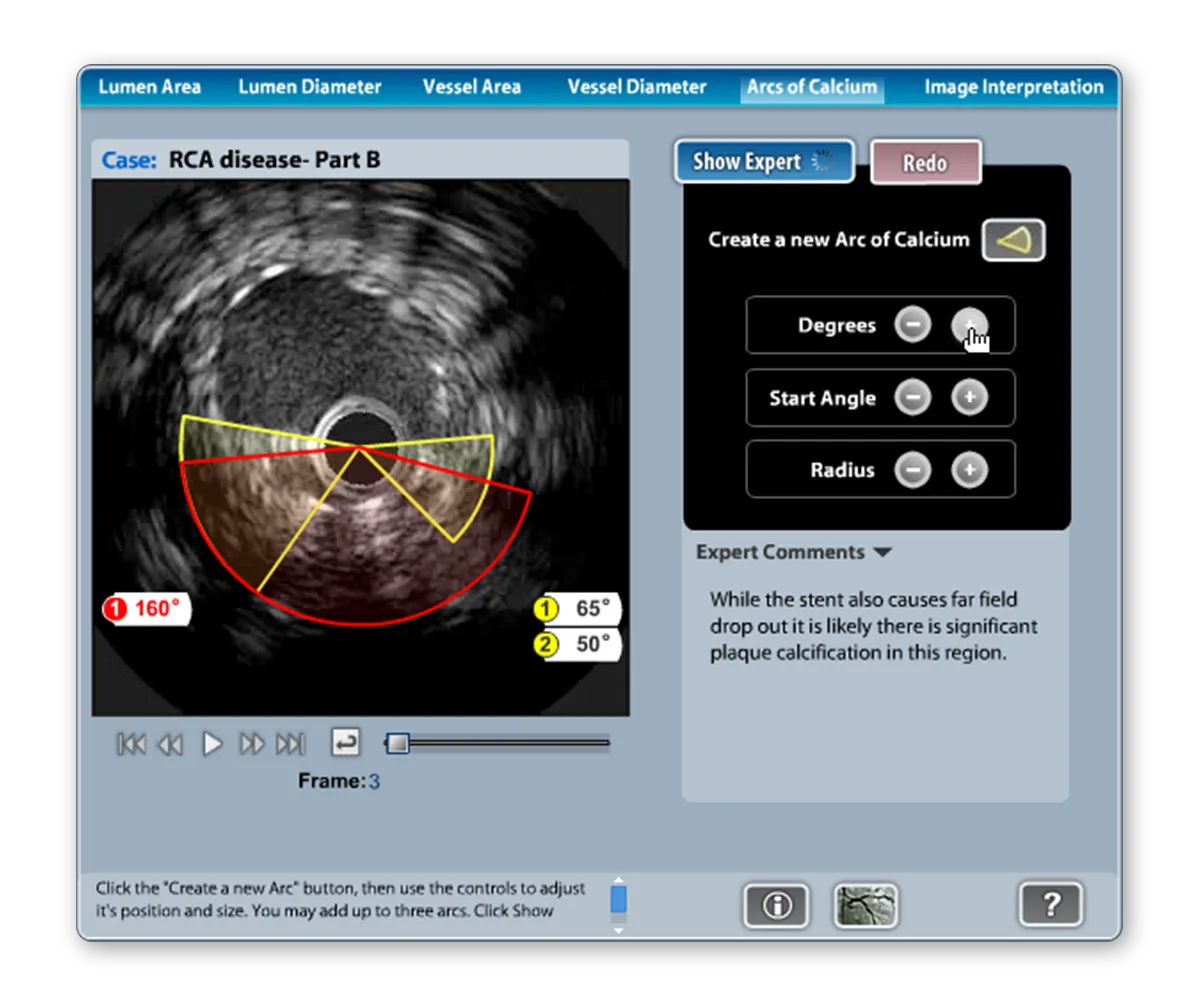

View the Case StudyThe Takeaway: Groundbreaking e-Learning apps that redefined a market, each winning an Adobe MAX Award (beating corporate behemoths like Toyota, Yahoo and TIAA-Cref), and delivered real-world simulation that helped cardiologists save lives.

View the Case StudySince 2003, thousands of projects have been submitted to Adobe for MAX Award consideration and winners include industry titans like Yahoo, Pepsi, T-Mobile, Nike, NASA, BMW, and eBay. Only three companies have won two awards: Yahoo, Interone Worldwide GmbH and Multiweb Communications. I am honored to have my work with Multiweb be in such impressive company. For both TeachIVUS and TeachCTA I was the primary architect, designer, and programmer.